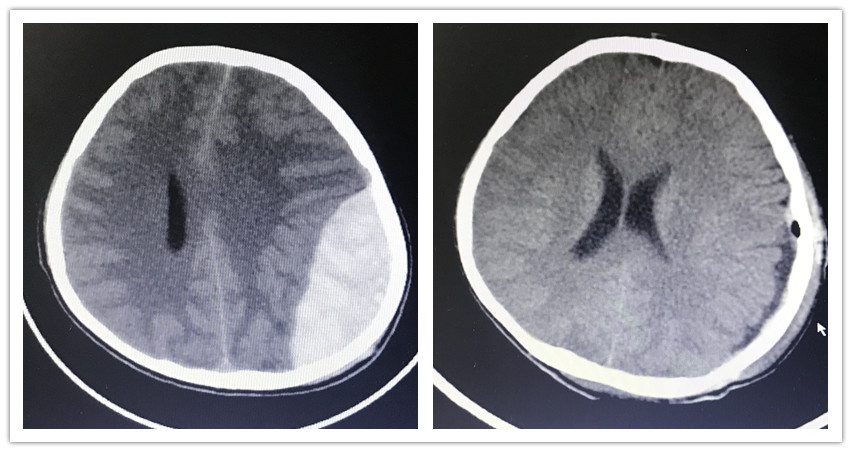

被送至医院时,小孙已出现瞳孔不对称、脑疝的症状,经CT检查,医生确诊其为硬膜外出血。血肿已压迫到了大脑,导致了小孙的昏迷,情况危急,需要立即手术。19日下午2时许,神经外科医生为其开展硬膜外血肿清除术,术中,清理出积血约100ml。

神经外科主任曾怀文介绍,硬膜外出血有“中间清醒期”,在外伤脑震荡导致“原发型昏迷”后,患者很快会清醒过来。过段时间(1小时到十几小时),随着出血增多,血肿压迫大脑,患者会再度出现意识障碍。小孙这次的情况就是硬膜外出血典型的“两次昏迷”特征。